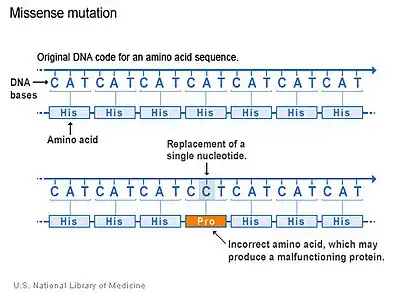

Mutated CSF1R Gene

There are several types of mutations that occur in genes. The majority of CSF1R genetic mutations in LENAS occur due to a type of mutation which is called a missense mutation.[3] Missense mutations occur when there is a change in a single amino acid of a protein. This single change can result in problems with functions of the protein, like the CSF-1 receptor. The kinase domain, which is the region of CSF-1 receptor where the mutation occurs, is altered and thus the normal function that activates other proteins is compromised and cannot stimulate cell signaling pathways properly.[3]

Although this is the primary type of mutation in LENAS, other types may occur as well but it is not as well understood for this disease.[3]

This genetic mutation is related to LENAS and said to be the main cause but how these lead to damage in the white matter and associated symptoms (cognitive and movement impairment symptoms) is still not fully clear.[3][7]